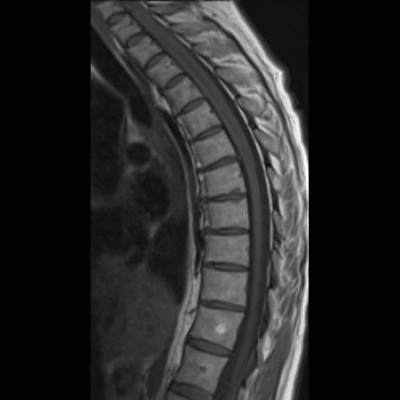

- (A) Torakal MRG’de sagital görüntülerde üst-orta torakal düzeyde T2A hiperintens (oklar), T1A izo-hipointens (ok) uzun segment ekspansil sinyal değişikliği izlenmekte olup sagital postkontrast T1A’da kontrast tutulumu mevcuttur (oklar). Bulgular longitudinal ekstensif transvers miyelit (LETM) ile uyumludur.

- Transvers miyelit sıklıkla santral gri cevheri etkileyen ve üç veya daha fazla vertebral gövde uzunluğunu etkilemektedir (LETM).

- Omurilik atrofisi ve ekspansiyon/ödem MS’e göre daha fazla görülür.

- Kontrast madde enjeksiyonu sonrasında neredeyse tüm akut NMO lezyonları, yamalı, düzensiz veya periferik olarak kontrastlanma gösterir.